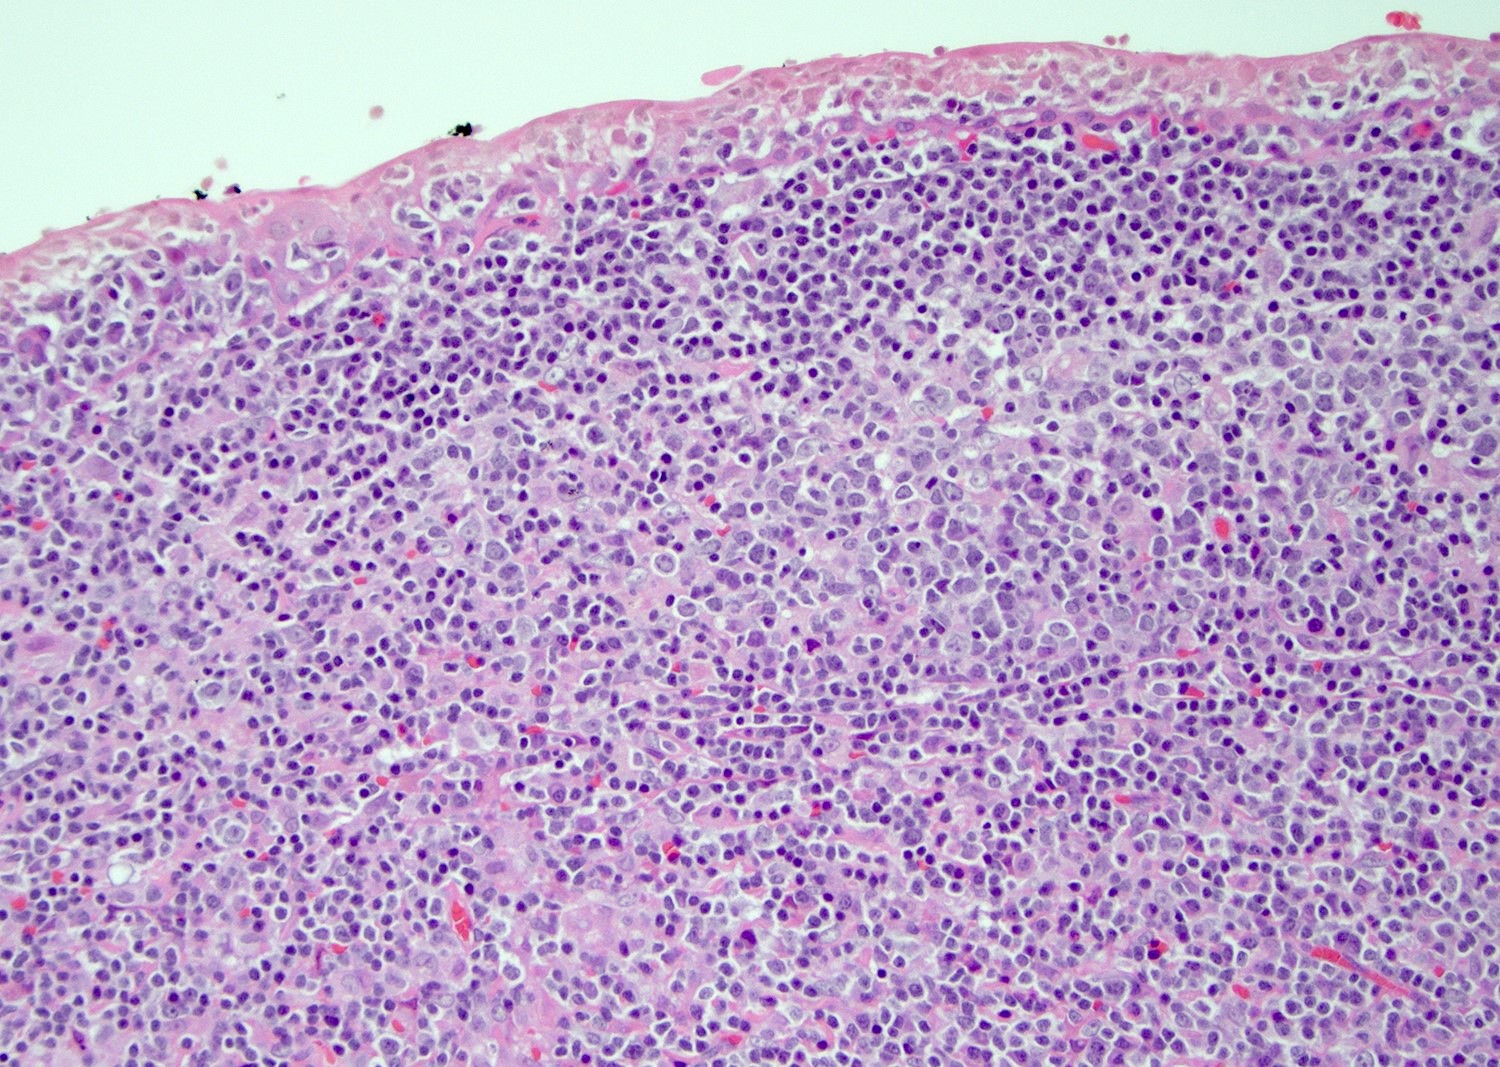

Microscopic (histologic) description

- Most cases show a unilocular cyst with a thin stratified squamous lining

- Ciliated, cuboidal or columnar epithelial lining is seen in rare cases

- Epithelium is surrounded by dense polymorphous lymphoid tissue with germinal centers and sinusoidal spaces

- Lymphocytes frequently permeate the epithelial cyst lining cells

Microscopic (histologic) images